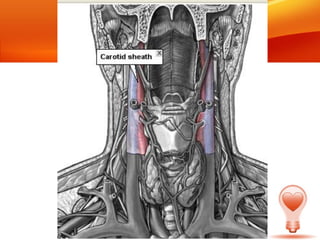

• Son los dos grandes troncos arteriales, que

junto a las arterias vertebrales proveen la

vascularización de las estructuras de la

cabeza y cuello.